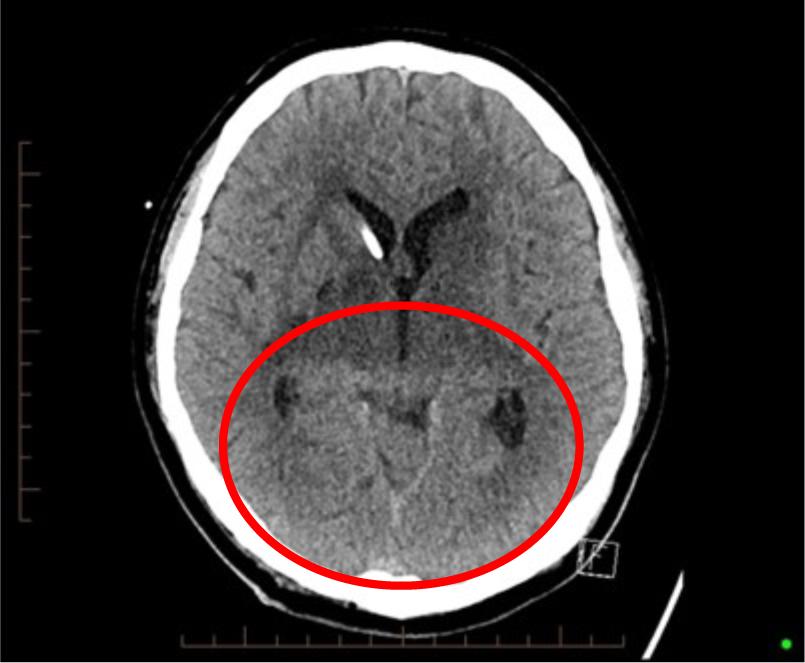

The final day commenced on the night shift of 1st-2nd March. It began with the previous shift handing over that Mr X’s current GCS was 10 (E4 V1 M5), with a high respiratory and heart rate. During the night shift, Mr X’s GCS dropped further, eventually reaching a GCS of 6, with sluggish pupils and vitals increasing significantly. At this point, another medical review was called. Throughout this period, the patient’s EVD remained patent, ruling out further hydrocephalus as the cause. Despite reluctance from teams, an intensive care team was eventually called, and an urgent CT head was arranged. To note, at this point, the patient was still for full resuscitation despite the potential poor outcomes. The patient’s wife was then contacted, she was informed of her husband’s status, and she arrived at the hospital to join his parents at his bedside. By 0645hrs, the patient’s GCS remained at 6, however he had become vitally more unstable, with a notable temperature of 39.5°C and heart rate of 189 beats per minute, with a non-responsive right pupil. Shortly after, he was accompanied to his CT scan.

On arrival back to the ward the neurosurgery team had arrived and we requested a review but were told his status was ‘not an acute concern’. We then rang his general medical team who were unaware of his deterioration. They quickly arrived at the ward and the results of the CT were discussed between teams. The CT showed a large brain stem stroke. The decision was made to have an urgent family meeting and a Chinese doctor was asked to translate for Mr X’s parents. The extremely unwell status of the patient was explained to the family and they were told “given his current clinical condition and context we do not believe he will recover”. The family were told that there was a high chance he would pass away today, and that no intervention would be beneficial. At this point Mr X’s wife became distraught and fainted. Resuscitation status was finally discussed with the family soon after and despite his parents wish for him to be resuscitated no matter the outcome; the final decision was made by his wife, as his next of kin, for him to be not for resus (NFR). The NFR status form was then filled out and Mr X confirmed officially as NFR. Throughout the day treatment was continued, the EVD was still patent, intravenous antibiotics and medications were still given with patients vitals decreasing throughout the day. At 1230 vitals were unable to be obtained, the patient was noted to be posturing, and at 1258 Mr X took a last breath and passed away surrounded by his family.

Pictured above is the result of the patient’s urgent CT head taken the morning that the patient passed away. It shows a large bilateral basal ganglia and thalamic infarct.